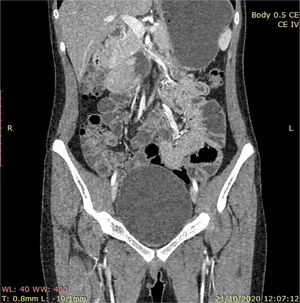

Presentamos el caso de una mujer de 18años referida por historial de dolor abdominal, hematemesis e intususcepción intestinal en dos ocasiones ameritando resección intestinal (80 y 50cm de yeyuno-íleon, respectivamente). Su historial heredofamiliar, perinatal y personales patológicos sin relevancia; se investigan hasta 3 líneas familiares previas, sin encontrarse evidencia de patologías tumorales, congénitas o neoplásicas. En la exploración se observan máculas hiperpigmentadas en los labios y en la cavidad oral. Enviada con múltiples reportes endoscópicos e histopatológicos, comentando poliposis gastroduodenal (hasta de 25-40mm), poliposis colónica atenuada (10-20) de hasta 40mm, con sospecha de cáncer; múltiples polipectomías. Histopatología: adenomas aserrados, adenoma tubulovelloso con displasia de alto y bajo grado en colon. Las revisiones concluyen pólipos hiperplásicos (gastroduodenales), adenoma «avanzado» tubulovelloso mayor de 1cm y adenoma hamartomatoso duodenal (fig. 1) La enterografía por tomografía axial computarizada (TAC) muestra dilatación de segunda y tercera porción de duodeno con masa irregular que realza al contraste, de aproximadamente 52×35mm (fig. 2). La tomografía craneal y la serie ósea metastásica no evidenciaron lesiones.